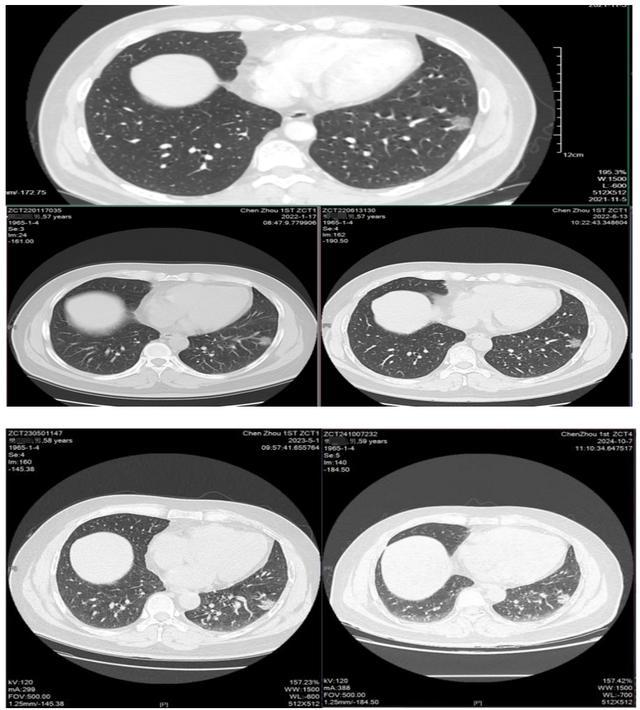

MTD汇聚了来自不同专科的顶尖医生,他们共同审阅了樊叔叔的病例资料,经过深入讨论,胸部肿瘤外科马忠厦博士凭借丰富的经验和敏锐的直觉,仔细阅樊叔叔本次增强CT及多次复查的CT后认为这个占位性病变有更高的可能性是恶性肿瘤。

(▲2024年肺部影像CT)